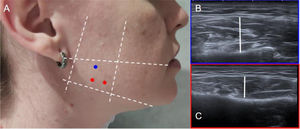

Technique. Injection of BT into the masseter has been performed without image guidance, using a quadrilateral defined by anatomical landmarks: the superior border from the earlobe to the corner of the mouth, the inferior border along the mandibular margin, and the anterior and posterior borders correspond to the masseter muscle’s limits.5,24 With ultrasound guidance, these anatomical landmarks can be used to explore the muscle and identify three injection sites. The temporalis muscle can also be examined, with two sites marked. Although injection into the masseter is generally sufficient for bruxism, experienced surgeons also recommend injecting the temporalis.5 (Fig. 6)

Figure 6.Example of anatomical landmarks for masseter infiltration. (A) Reference points for BT injection into the masseter, with the anatomical landmarks described in the body text, marked by white dotted lines. On the right, ultrasound anatomical sections corresponding to the most superior (B) and most inferior (C) level, where the masseter muscle is visualised (thickness indicated by a white line).

- 2

Dosage. It is recommended to dilute 100 U of BT in 2 ml, yielding 10 U per 0.2 ml. A volume of 0.2 ml is infiltrated at each of the three marked points in the masseter and at the two marked points in the temporalis on each side.5,24